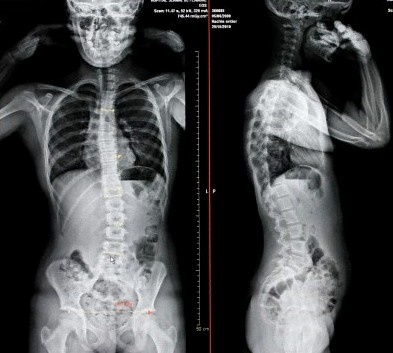

脊骨側彎檢查X光,從X光片中找出脊骨側彎的弧度

用垂直線來量度脊椎的彎位